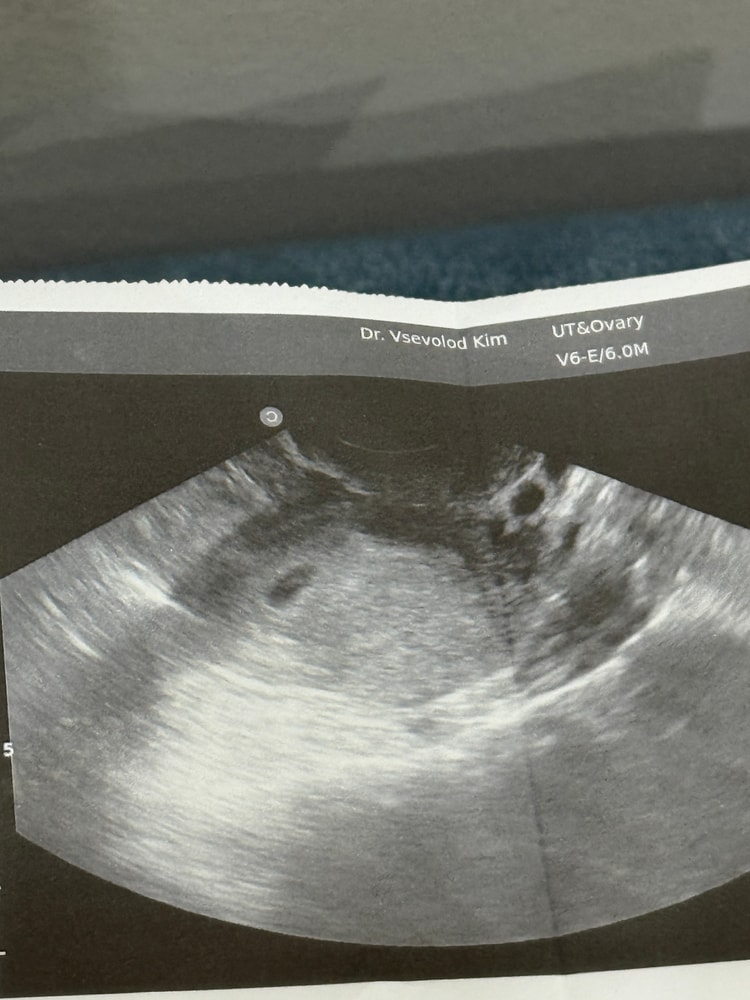

12ДПО положительный тест и ощущения

В общем, с 10дпо тест полосатится. Принимаю утрожестан. Сегодня уже 12 дпо, из ощущений почти каждые 2-3часа резкий прилив голода, желудок сосет прям) грудь болит) как думаете не рано ли началось то что желудок сосет сильно каждые 2 часа ? ))